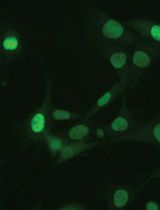

TRIPLE (Insulin, Glucagon and EGFP) Immunofluorescence Staining Protocol in Pancreas

Cover of Nature Cell Biology, featuring study using the protocol.